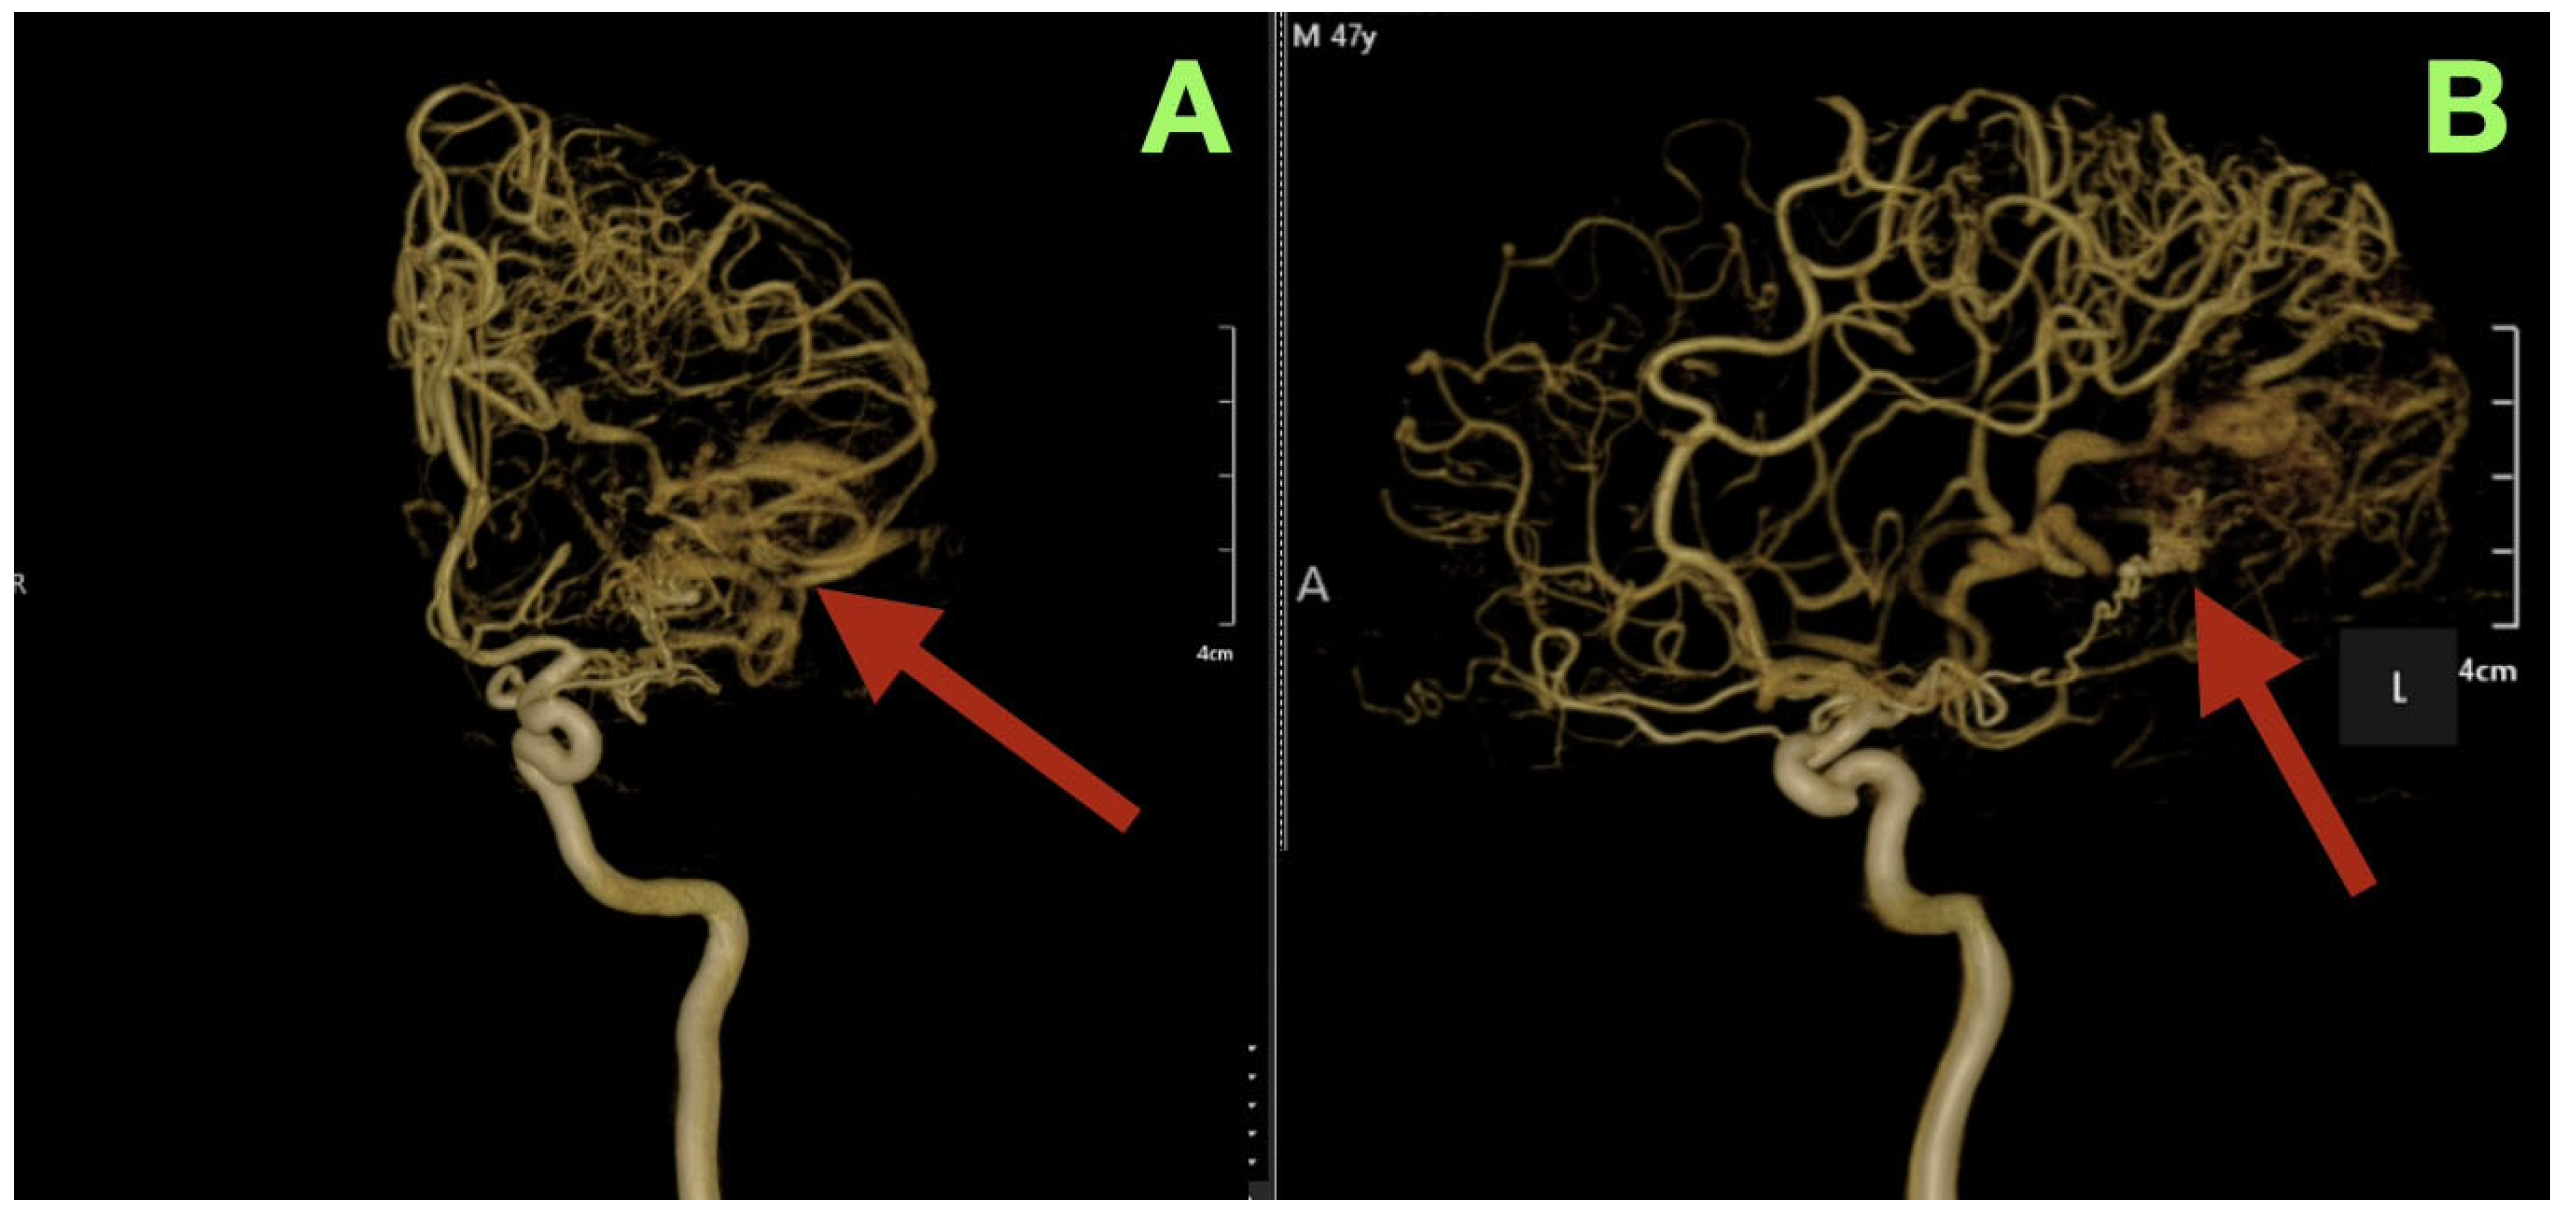

Angiographic studies, particularly selective cerebral angiography, utilizing bilateral internal carotid and left vertebral artery injections established a comprehensive, detailed vascular map of the suspected lesion clinically determined to be an AVM. Selective cerebral angiography established the presence of a compact, high-flow left temporo-parieto-occipital AVM of approximate dimensions 40 × 30 mm in size. The AVM nidus was located deep to the confluence of the posterior superior temporal, angular, and lateral occipital gyri, which is an anatomically unique location representing the crossroads of the posterior perisylvian cortex, visual association areas, and posterior inferior parietal lobule (Figure 1A–D).

Arterial Feeders

The AVM was found to receive blood supply from four different vascular territories: distal posterior cerebral artery (P4) branches from the calcarine and lingual cortices, distal middle cerebral artery (M4) branches from the temporal lobe, a branch from the anterior cerebral artery (A4) from the medial surface of the hemisphere, and a small twig from the superior cerebellar artery ascending along the tentorial edge (Figure 1A–D and Figure 2A,B). These multiple and diverse arteries converge and create a complex multi-directional shunt that supports high velocity flow and maintains parenchymal perfusion through inter-territorial anastomoses. The MCA feeders penetrate the posterior Sylvian fissure, which correlates with the patient’s expressive language hesitancy and phonemic errors. The PCA branches course through the temporal horn roof, which correlates with the patient’s right inferior quadrantanopia. The ACA feeds the superior aspect of the nidus bordering the paracentral lobule and correlates with the mild contralateral pyramidal hyperreflexia.

Venous Outflow

The AVM drains through two main channels creating a dual-drainage system. A superficial cortical collector ascends obliquely to the superior sagittal sinus via the vein of Trolard. An additional channel of venous outflow is an inferior-lateral trunk that ascends to the transverse-sigmoid junction via a dilated vein of Labbe (Figure 1C,D). Both veins are ectatic but smooth walled and simultaneous opacification confirms high flow and low resistance shunting with no evidence of thrombosis or segmental stenosis. There were no intranidal aneurysms, venous varices or aneurysmal dilatations of the feeding arteries.

Figure 1. Preoperative digital subtraction angiography (DSA). (A): Lateral projection during selective left internal carotid injection demonstrates a compact, high-flow nidus (arrow) centered at the temporo-parieto-occipital junction. The arterial convergence from distal MCA and PCA branches is clearly visualized, with early venous filling consistent with a high shunt volume. (B): Anteroposterior projection highlights the dense arteriovenous network occupying the posterior perisylvian region (arrow). Multiple feeders from M4, P4, and A4 segments converge toward the nidus, producing an intricate lace-like configuration typical of compact high-flow AVMs. (C): Late arterial phase delineates the dual venous drainage (arrow), with a superior cortical outflow ascending to the superior sagittal sinus and a secondary temporobasal collector directed toward the transverse-sigmoid complex. (D): Venous phase confirms synchronous opacification of both drainage routes (arrow), demonstrating the bidirectional flow pattern and the absence of venous outflow restriction. The preserved parenchymal perfusion surrounding the nidus suggests a stable hemodynamic equilibrium between the AVM and eloquent cortical territories.